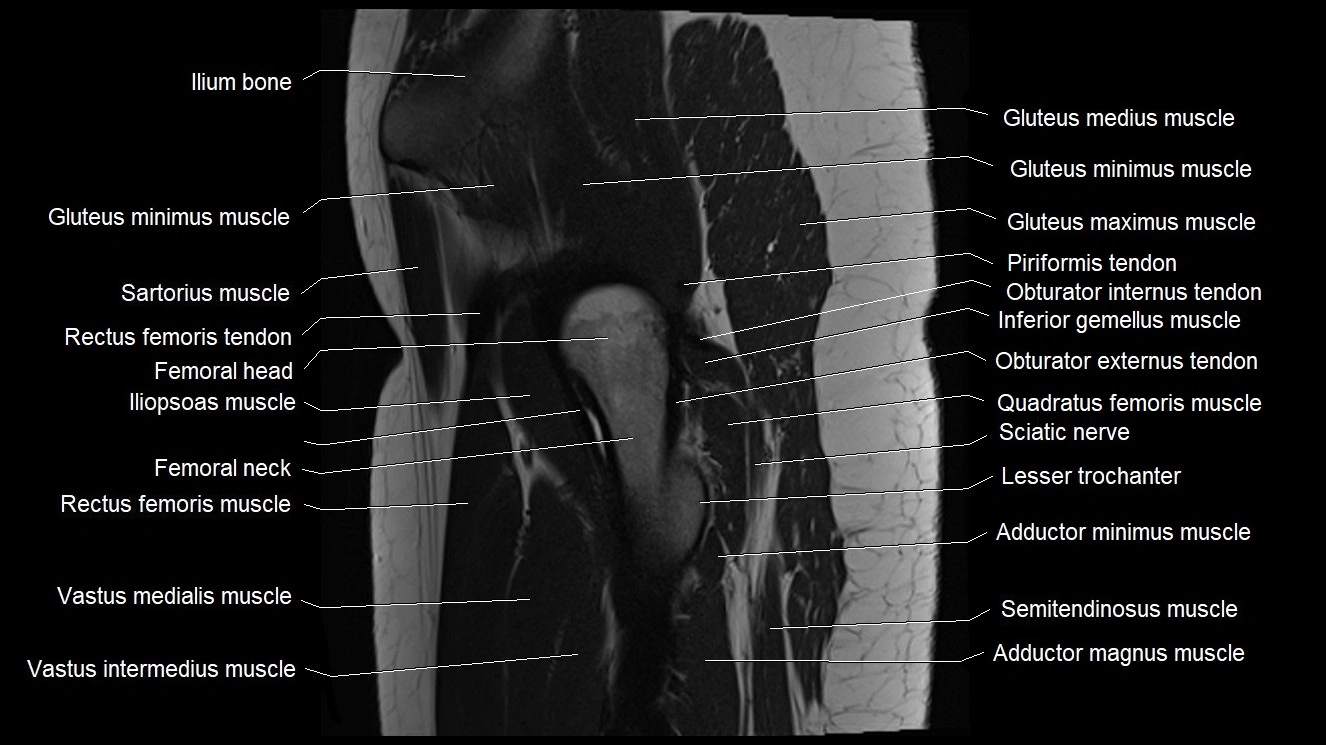

- Gluteus medius muscle

- Gluteus minimus muscle

- Gluteus minimus tendon

- Iliopsoas muscle

- Inferior gemellus muscle

- Lesser trochanter

- Neck of femur

- Quadratus femoris muscle

- Rectus femoris muscle

- Rectus femoris tendon (Proximal tendon of rectus femoris)

- Sartorius muscle

- Vastus intermedius muscle

- Vastus medialis muscle